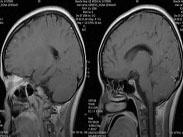

結核性腦膜炎治療

• 結核性腦膜炎

628健康網為您分享有關結核性腦膜炎的癥狀,結核性腦膜炎的治療方法,結核性腦膜炎的預防知識,結核性腦膜炎的癥狀圖片,結...